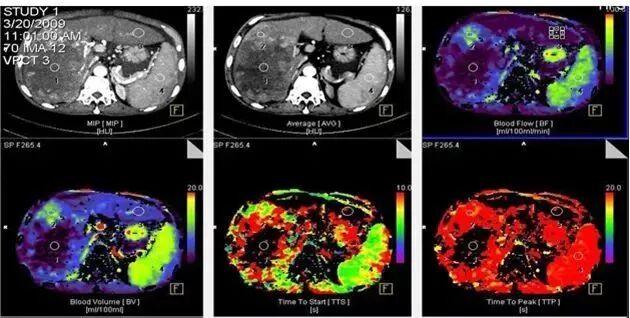

西门子CT提供包括BF、BV、TTS、TTP在内的多种灌注参数及图像,为临床诊断肿瘤性质,早期评估手术效果提供诊断依据。